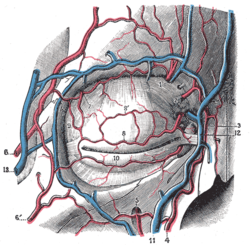

Qovoq — umurtqalilar oilasining koʻzlari atrofidagi teri qoplamasi. Qovoq koʻzni turli tashqi zararlardan himoyalaydi, koʻz soqqasini suyuqlik (koʻz yoshi) bilan qoplab turishda yordam berib, uni toza tutishda muhim rol oʻynaydi. Sutemizuvchilarning qovoqlari chetida koʻpincha kipriklar oʻsgan boʻladi.